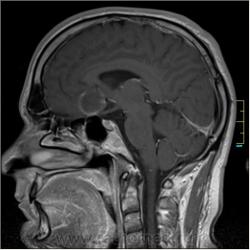

Cor T1:

частично функционирующая аневризма

Иначе говоря, аневризма с хронической геморрагией, т.к. мы видим фракции крови различного возраста.

Постепенное пристеночное образование тромбов приводит к появлению типичного для аневризмы феномена -слоистости МР сигнала в полости аневризмы. Данная картина демонстрирует слоистый характер тромботических масс в полости аневризмы .Функционрирующая часть имеет низкий сигнал во всех режимах сканирования. Дополнительно-перифокальный отек.

А может более корректно интерпретировать как частично тромбированная аневризма... Уж коь речь идет о фракциях, ну то есть о тромбе по сути.... Ну и плюс перфокальный отек головного мозга (вероятнее цитотоксический+вазогенный).